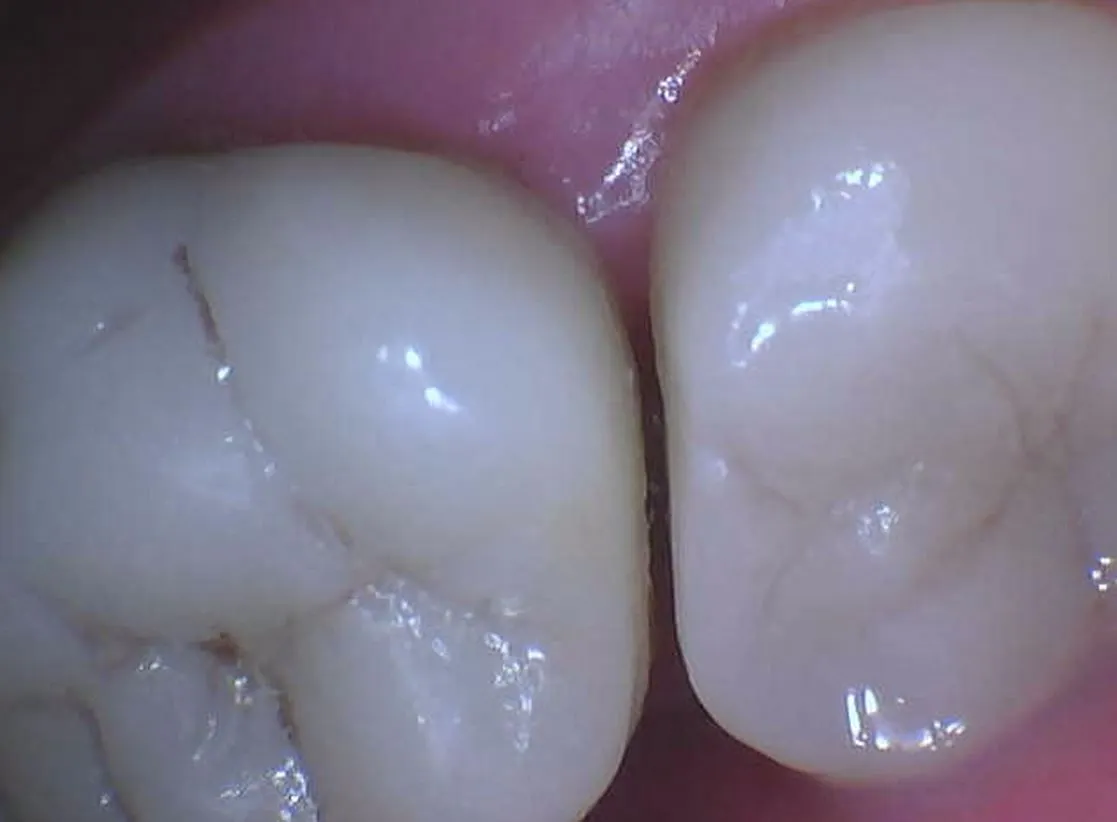

Intaoral photo showing a gap between teeth. Gaps like these often cause food to trap which usually leads to discomfort, tooth movement and decay.

We very often use intraoral cameras at Pocono Pines Dental. An intraoral camera is an amazing diagnostic tool for viewing details of your teeth so we devise a treatment plan, together! The small, wand-like camera gives us the ability to capture pictures inside your mouth and then view the pictures on a computer monitor right in the dental operatory. We can get a closer look at any potential issues or problems. In addition, you will have the ability to see for yourself, first hand the same images we are seeing. We can point out areas where more brushing attention is needed, where there are stains, chips, fractures, cavities, heavily restored teeth, tissue lesions etc. These digital images are also excellent for gaining procedure reimbursement from insurance companies. We can also get a much better view of hard to see areas and monitor teeth we have previously restored.